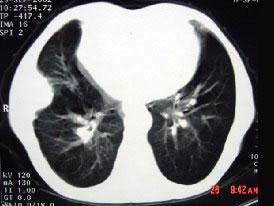

CT图像,最可能诊断为 ( )A.右肺肺占位B.右侧胸膜良性病变C.肋骨病变侵犯胸壁D.膈膨升E.纵隔肿块

问题 CT图像,最可能诊断为 ( )

选项 A.右肺肺占位 B.右侧胸膜良性病变 C.肋骨病变侵犯胸壁 D.膈膨升 E.纵隔肿块

答案 B